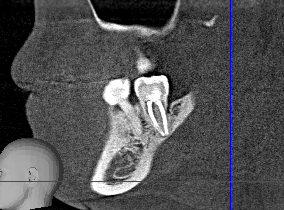

>>1614423

протрузия - резцы вперед торчали, типа на три части челюсть пилят и куски поворочавиют и в ужное положение ставят.